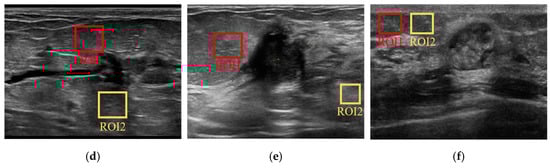

3.1.2. Experiments on Real US Images

| US Image 1 | US Image 2 | US Image 3 | ||||

|---|---|---|---|---|---|---|

| ROI-1 | ROI-2 | ROI-1 | ROI-2 | ROI-1 | ROI-2 | |

| GIF | 21.4976 | 9.2061 | 10.8467 | 13.0614 | 35.9332 | 5.9912 |

| Lee | 29.2625 | 10.4813 | 14.4238 | 15.9266 | 64.1074 | 12.0654 |

| Frost | 27.8564 | 10.2496 | 13.8844 | 15.5675 | 57.7815 | 10.8900 |

| Gaussian | 29.1324 | 10.4348 | 14.2828 | 15.7657 | 100.7314 | 18.0757 |

| Bitonic | 33.0059 | 10.9510 | 15.8999 | 16.9290 | 93.1637 | 17.1567 |

| WLS | 43.3577 | 13.4256 | 18.7544 | 19.8149 | 223.7867 | 16.4700 |

| ADMSS | 21.5470 | 9.0889 | 15.2790 | 11.9555 | 34.6900 | 34.5554 |

| SRAD | 34.6307 | 11.2436 | 14.9490 | 16.5835 | 142.7407 | 14.8044 |

| SRAD-Bayes | 34.5921 | 11.5086 | 14.9769 | 16.5751 | 142.7472 | 14.8048 |

| SAR-BM3D | 29.5615 | 10.4383 | 14.8830 | 16.6464 | 77.9813 | 14.2999 |

| Proposed | 36.7761 | 11.8523 | 15.2899 | 16.8020 | 199.1937 | 14.9264 |

| US Image 4 | US Image 5 | US Image 6 | ||||

| GIF | 10.2034 | 14.9478 | 50.4453 | 37.1283 | 18.7762 | 28.4937 |

| Lee | 12.1528 | 18.4038 | 40.1959 | 31.6776 | 15.0236 | 22.5928 |

| Frost | 11.8881 | 17.6928 | 38.4305 | 30.5600 | 14.5445 | 21.8719 |

| Gaussian | 13.7501 | 20.9189 | 39.5283 | 31.3656 | 16.9306 | 25.8945 |

| Bitonic | 12.4643 | 20.1317 | 45.3041 | 33.4917 | 15.5404 | 25.1755 |

| WLS | 17.7059 | 29.5167 | 67.1322 | 51.5178 | 26.3737 | 38.0826 |

| ADMSS | 10.8299 | 15.8205 | 47.8042 | 34.3954 | 15.2125 | 23.7334 |

| SRAD | 12.8285 | 19.8875 | 40.4638 | 31.8749 | 16.8350 | 25.5281 |

| SRAD-Bayes | 12.9219 | 19.8853 | 40.5353 | 31.9014 | 16.8584 | 25.4082 |

| SAR-BM3D | 11.7274 | 18.5588 | 42.4447 | 32.6953 | 14.7869 | 23.8162 |

| Proposed | 13.6607 | 22.2331 | 48.3190 | 35.7300 | 18.2626 | 29.0689 |